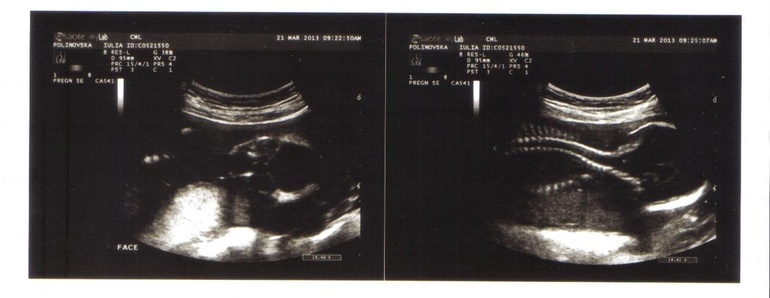

17.05.13 узи. Последнее наше узи. Плацента встала на место - это хорошо. Но нас озадачили, на узи была другая женщина и она сказала, что ей больше похоже на мальчика, но ребеночек очень двигается и она отправит запрос экспертам (или кому ...) и они результаты уже врачу переправят.

Сказать честно я немного расстроилась. Я уже свыклась с девочкой, мы уже и имя придумали и по имени обращались к пузожителю, хотя какой то червь сомнений жил во мне все равно. А еще было очень забавно, потому что во время узи, крошка был очень активный и толкал ту штучку которой узи делают.